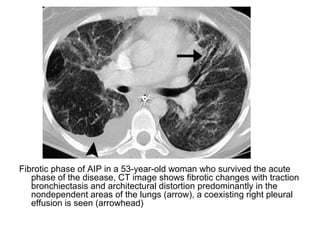

Fibrotic phase of AIP in a 53-year-old woman who survived the acute

phase of the disease, CT image shows fibrotic changes with traction

bronchiectasis and architectural distortion predominantly in the

nondependent areas of the lungs (arrow), a coexisting right pleural

effusion is seen (arrowhead)